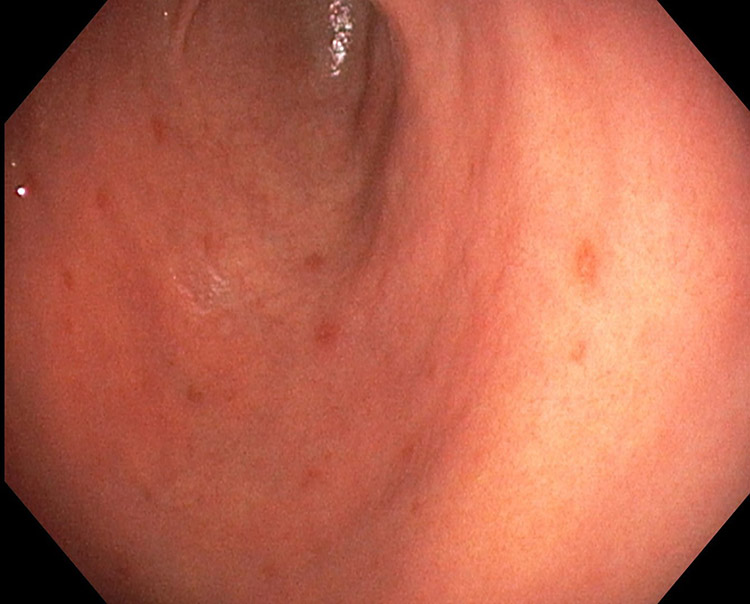

胃炎は、胃の内側を覆う粘膜に炎症(ただれ・赤み)が起きている状態の総称です。一時的な刺激で起こる「急性胃炎」と、長く続く「慢性胃炎」があり、原因によって対応が変わります。

- 胃カメラ(上部消化管内視鏡):胃炎の程度や潰瘍・出血の有無を確認します。必要に応じて生検(組織検査)を行い、他の病気が隠れていないかも確認します。

※胃の症状があっても、胃カメラで強い炎症が見つからない場合は、別の病気(例:機能性ディスペプシア)を考えて治療方針を調整します。